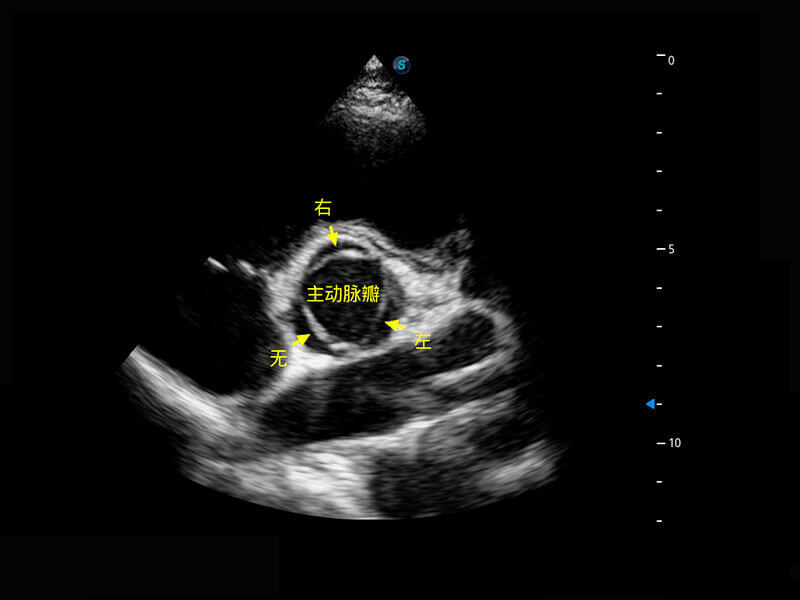

新生儿脊髓圆锥

新生儿心脏